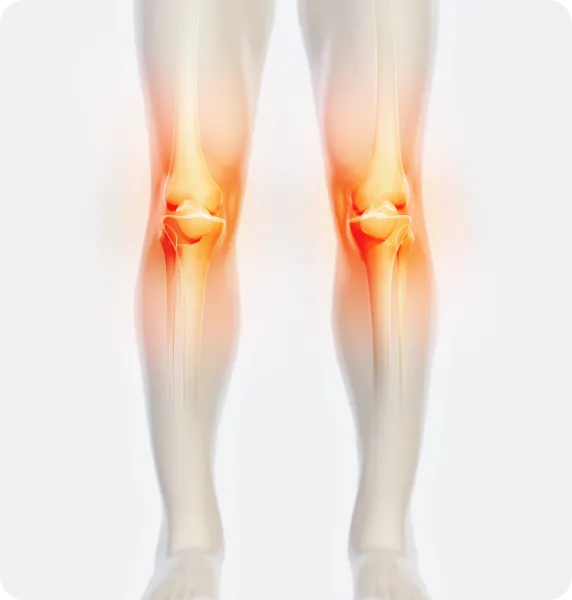

무릎

무릎 관절 안팎으로

휘거나 틀어짐

휜다리는 현재 통증이 없다 하더라도, 장기적으로 관절과 신체 전반에 다양한 문제를 초래할 가능성이 있습니다. 예를 들어, O다리(내반슬)는 무릎 안쪽 관절에, X다리(외반슬)는 무릎 바깥쪽 관절에 비정상적인 하중을 가해 연골 마모를 촉진하고 관절염 발생 위험을 높일 수 있습니다. 이러한 다리 정렬 불균형은 골반 틀어짐, 척추 정렬 이상 등을 유발하며, 허리 통증, 보행 곤란, 피로 누적 등으로 이어질 위험이 있습니다. 시간이 지나면서 관절과 인대 사용에 따른 손상이 누적되고, 만성 통증으로 드러날 가능성도 크기 때문에 조기 교정을 통한 예방적 관리가 필요합니다.

• 체중부하가 다리 안쪽(내측)에 집중되어 내측 관절의 압력증가로

무릎관절의 퇴행성 변화와 통증을 초래

• 체중 부하가 다리 바깥쪽에 집중되어 외측 관절의 압력증가로

무릎 통증, 불안정성, 관절 손상을 유발할 수 있음